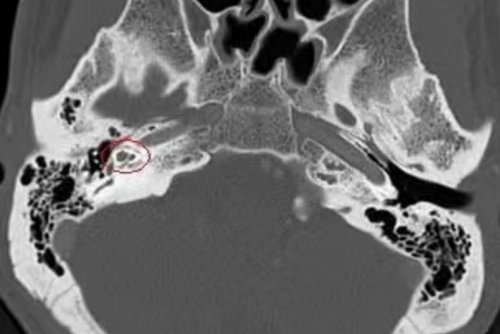

(影像资料提示耳内病灶部位)

“入院时,患者右耳听力下降更为明显,建议先行耳内镜下右耳鼓室探查,术中探查若证实为耳硬化症,则建议行人工镫骨手术来恢复患者听力。”在冯永教授的带领下,耳鼻咽喉头颈外科耳科专家团队杨中纯博士、康晓明博士为刘先生进行耳内镜下右耳鼓室探查,术中证实锤骨砧骨活动度好,镫骨固定不动,与术前考虑的一致,确诊为耳硬化症。目前,临床上针对耳硬化症最常用、有效的治疗方式是手术治疗,需在显微镜下或耳内镜的辅助下,将镫骨切除,然后安装人工听骨。

诊断明确后,手术团队为刘先生进行“耳内镜下右人工蹬骨植入术”。术中,在进行镫骨底板钻孔时突然出现大量脑脊液井喷,考虑外淋巴液与脑脊液之间存在异常通道的可能,而耳硬化症并发脑脊液耳漏在临床上极为罕见,文献中也仅有零星报道,我院也是首次遇到镫骨打孔后脑脊液井喷的情况,无疑给手术带来更大的挑战和难度。冯永教授凭借丰富的临床经验和精湛的技术成功取出原来已经固定的病变镫骨,并封闭前庭窗修复脑脊液耳漏后植入人工镫骨,整个过程如履薄冰,手术顺利完成,术后刘先生初测听力明显好转,没有脑脊液耳漏和眩晕的情况,过几天即可出院回家。